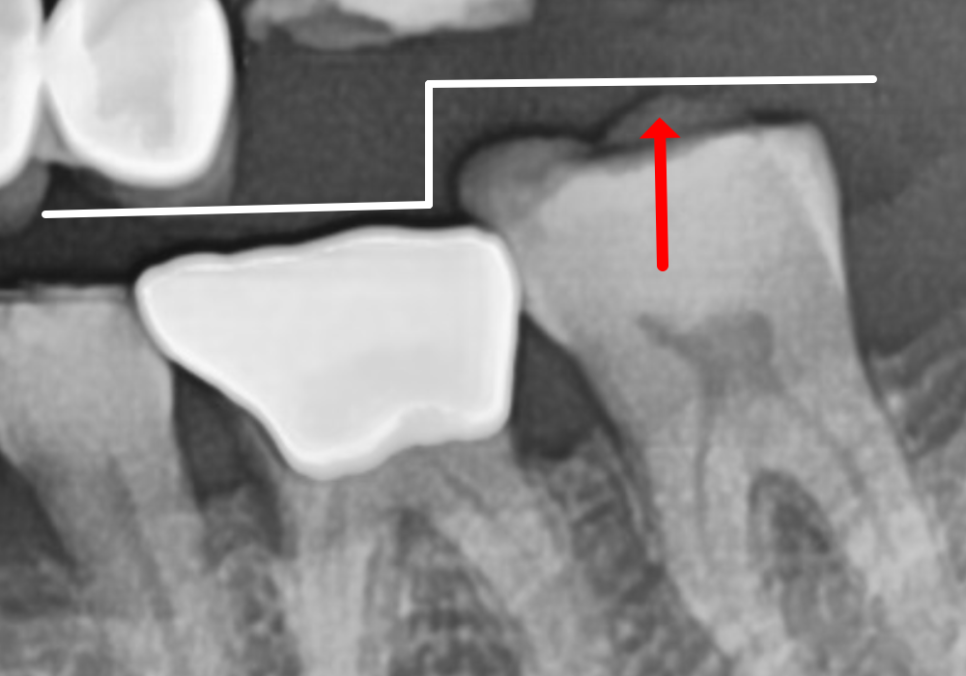

방사선 사진을 살펴보니,

옆 치아들에 비해 잇몸뼈가 많이

낮아진 걸 확인할 수 있었습니다.

더 자세히 살펴보기 위해

CT를 확인해 보았습니다.

CT 상에서 검게 투과되어 보이는 부분들이

모두 염증인데,

이미 치아를 지탱할 잇몸뼈가 상당 부분

녹아 없어진 상태네요..

특히 입천장 쪽 잇몸뼈가 소실되면서

치아를 받쳐주는 '지지대'가

아예 사라진 상황이었는데요,

결국 뿌리가 뼈에 간신히 걸쳐 있다 보니,,

치아는 앞쪽으로 뻗치면서

힘없이 아래로 내려앉을 수밖에 없겠죠.